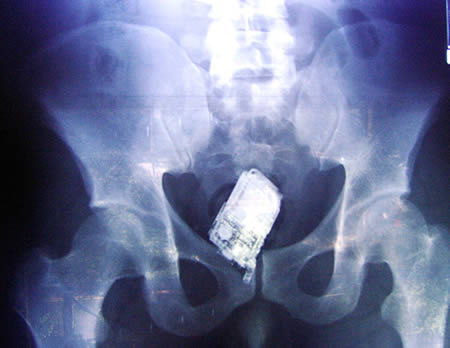

این تصویر یک موبایل در انتهای روده یک دزد هست.این آقا دزده عضو یک دسته گنگستر هست و می خواسته این موبایل رو با خودش داخل زندان ببره.